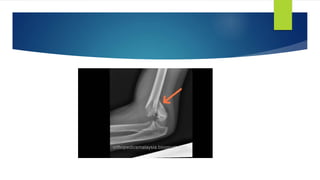

 AP view

Baumann angle

 lateral